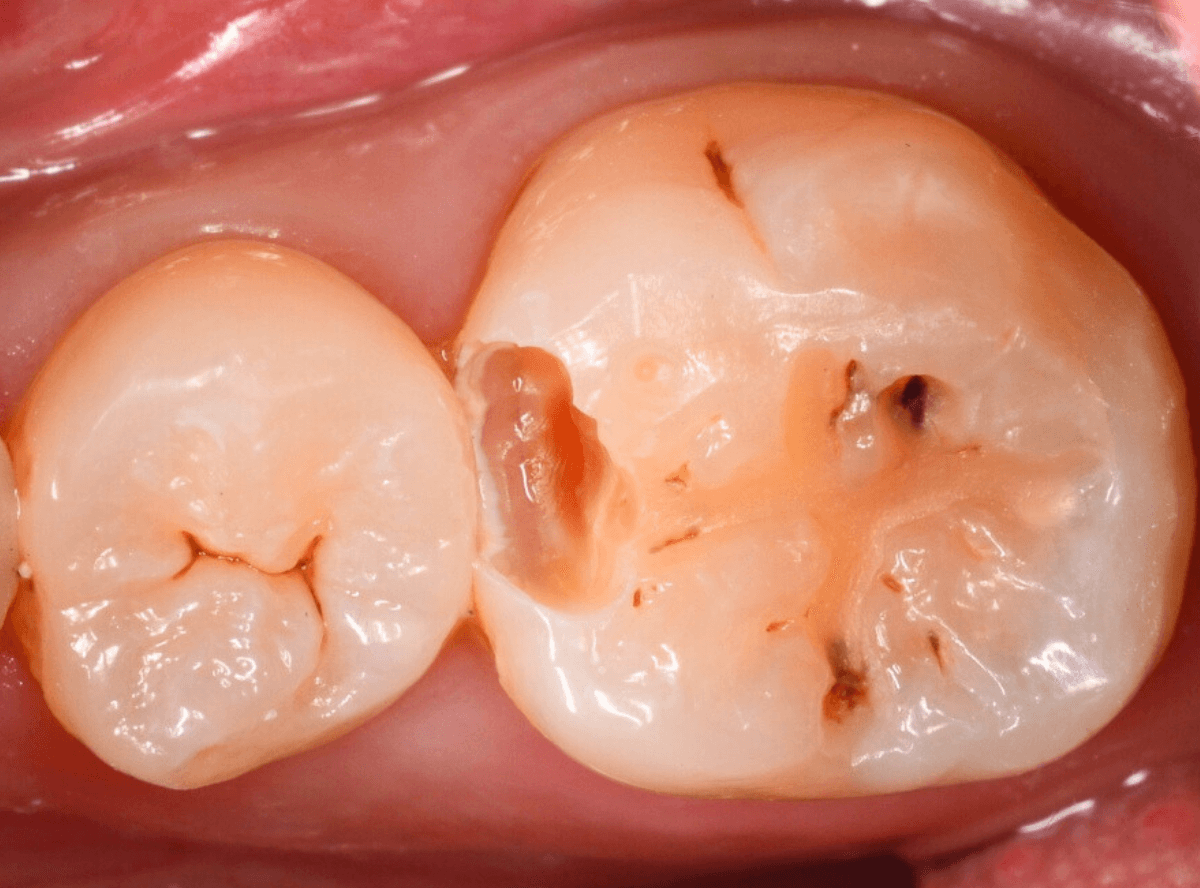

Case.23 歯のすきまから両側が大きな虫歯

「下の奥歯が痛む」という訴えで来院された患者さんのケースです。

目視でも、手前の奥歯がかけていて、中で虫歯が広がってるであろうことは予想できます。

ピンセットで歯を叩いてみても、手前の奥歯が痛むようです。

レントゲン写真で確認します。

青い線が神経、赤い線が虫歯の範囲です。

奥歯の方がより深い虫歯に見えますが、再度打診で確認したところ、やはり手前の奥歯が痛むそうです。

状況から、まず手前の奥歯から治療となりました。

麻酔をして、手前の奥歯のレジンを慎重に外します。

前に虫歯の治療をした時点で、神経スレスレの状態でしたので、削りすぎないように慎重にレジンを外さなければいけません。

レジンを外して、う蝕検知液で確認します。

レジンの中で虫歯が進行していたのがわかります。

慎重に全ての虫歯を除去しました。

何とか、神経が露出せずに済んでいます。

お薬をつめて、セメントで蓋をして経過観察します。